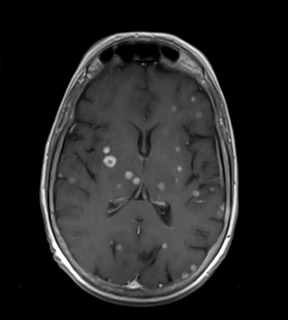

Prueba diagnóstica no invasiva que consiste en la obtención de imágenes de alta definición anatómica de las órbitas mediante el empleo de un campo electromagnético y ondas de radio (con un emisor y un receptor). No utiliza radiación ionizante. Indicaciones: visión doble, traumatismo, sospecha de tumor, hipertiroidismo.